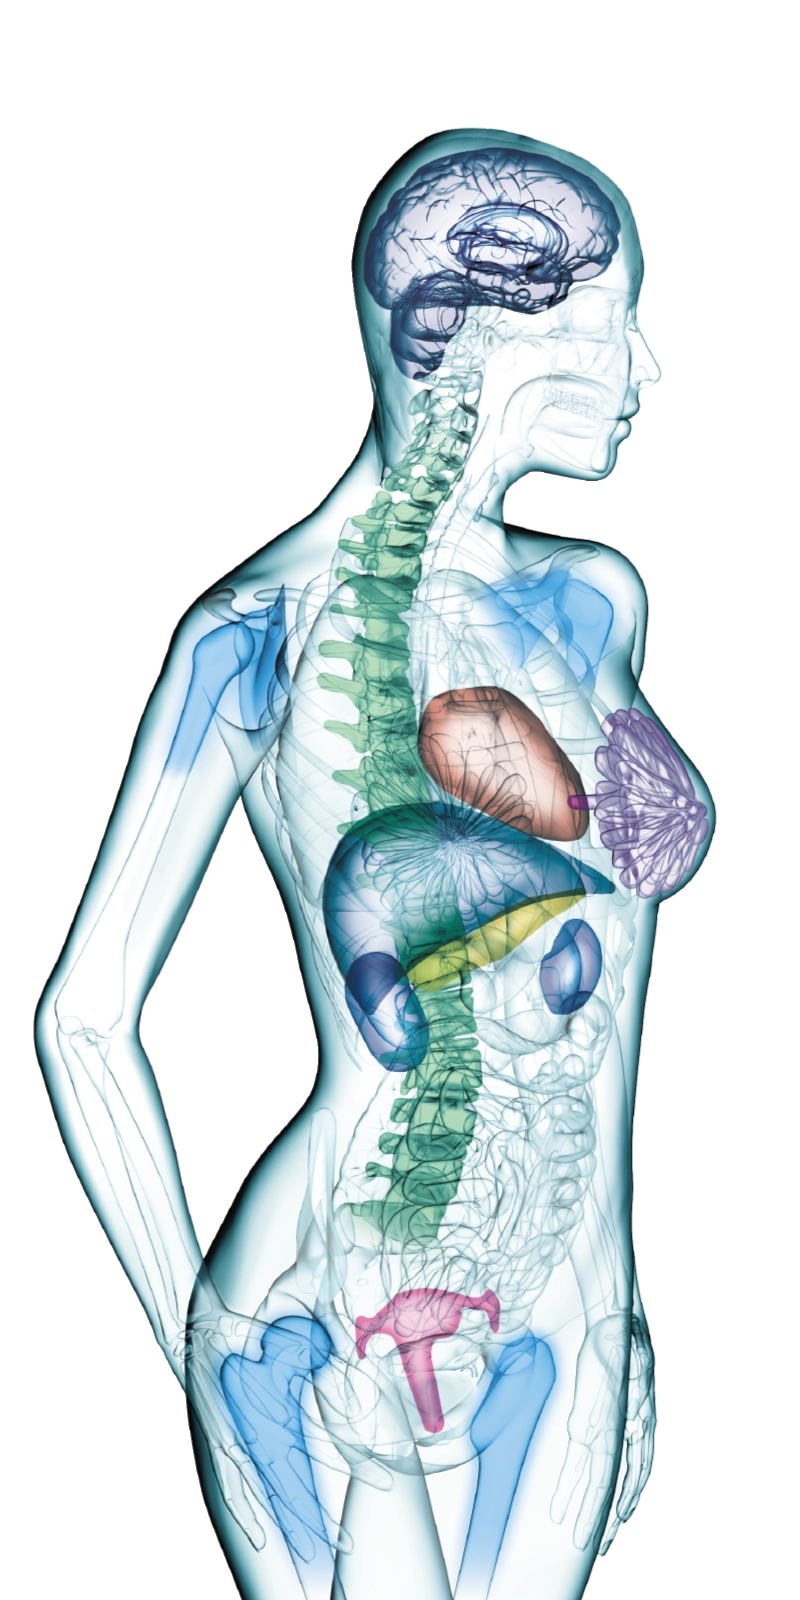

Wide bore and variety of coils to support comfortable examinations

The 70cm diameter wide bore improves comfort for patients. To match the wide bore, we also paid close attention to the size of the patient table to ensure a space of 62 cm for the moving part of the patient table. This allows for quick adaption to imaging in a variety of patient positions.

The ECHELON Synergy ZeroHelium is equipped with a flexible head and neck coil that allows one-action setup via sliding installation, as well as a Flex coil that provides wide and flexible coverage of the imaging area. This enables flexible adaptation to different part of body.